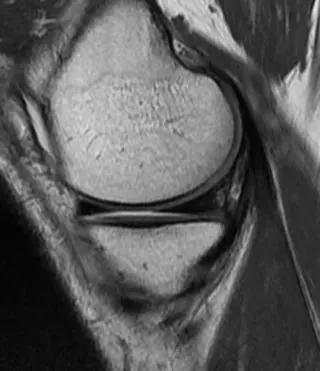

On sagittal and frontal images, the normal meniscus is triangular in hypointense. On the most lateral sagittal image, the meniscus is a "bow-tie" structure consisting of a mid-sagittal section combined with the anterior and posterior horns (Figure 1).

Figure 1 Normal MRI appearance of the medial meniscus. Proton density-weighted sagittal view: The anterior and posterior meniscal angles are homogeneous hypointense triangles. The meniscus is bow-shaped and consists of sections of the middle section that connect its anterior horns in front of it and its posterior horns behind it.